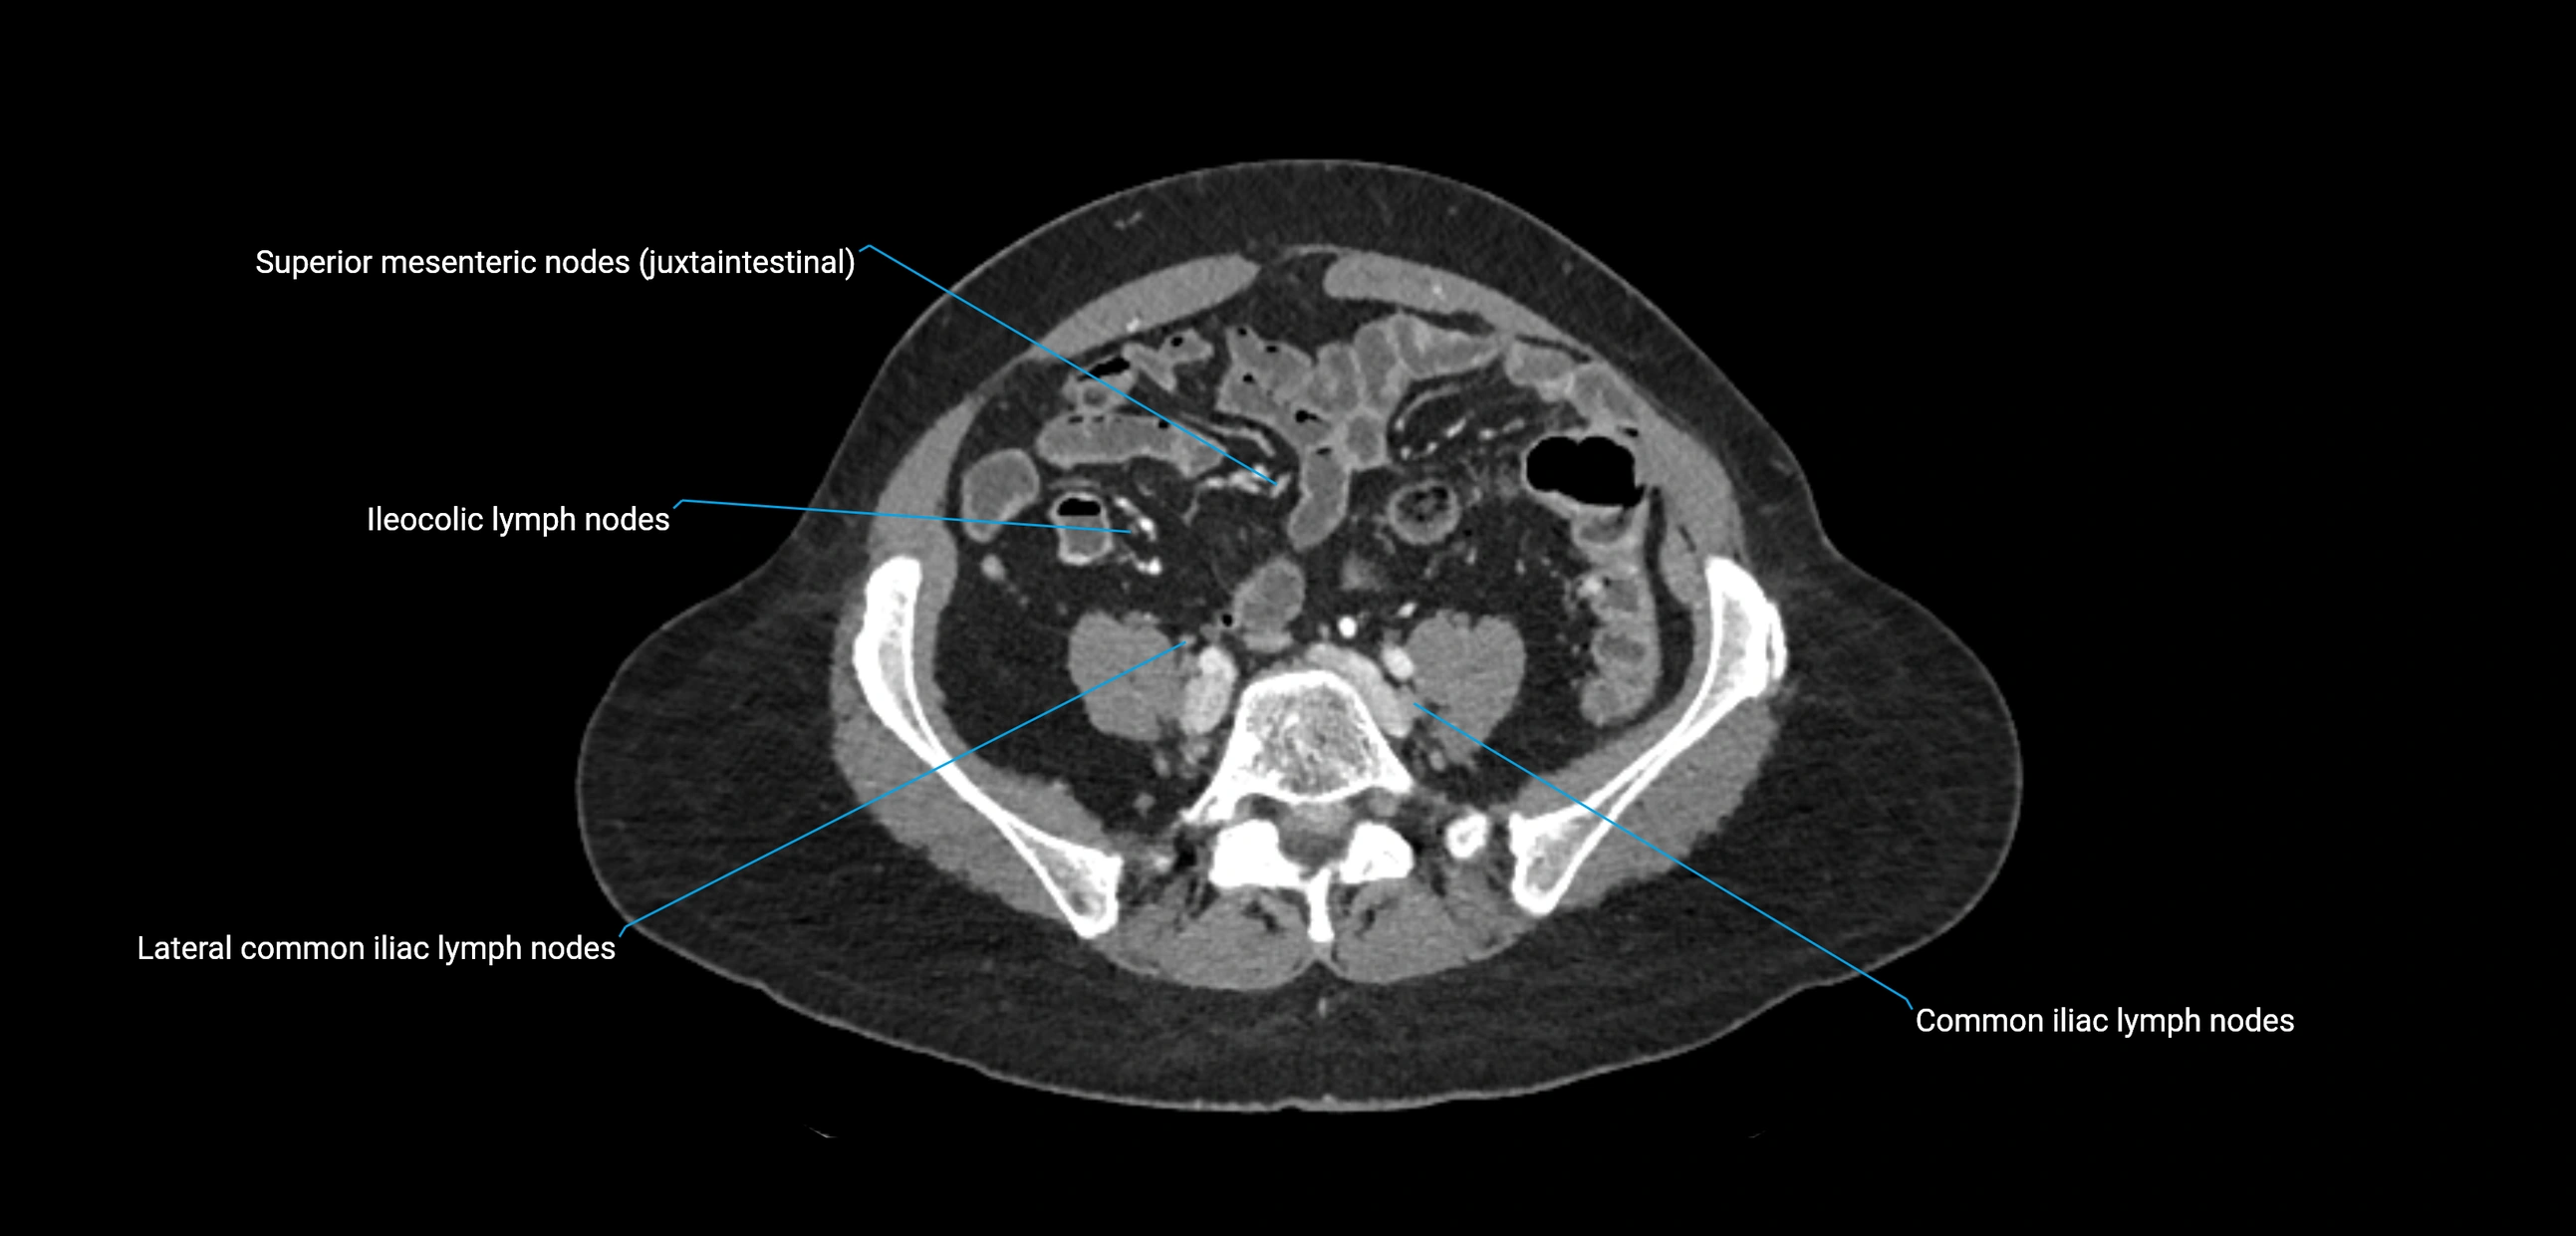

CT Appearance

CT Pre-Contrast:

• Nodes appear as soft-tissue density nodules adjacent to the aorta and IVC

• Calcification may be seen in chronic infections (e.g., tuberculosis)

CT Post-Contrast:

• Normal nodes enhance homogeneously

• Malignant nodes may show heterogeneous enhancement, central necrosis, or conglomerate formation

• Size >1 cm short axis is suspicious, though morphology and distribution are equally important